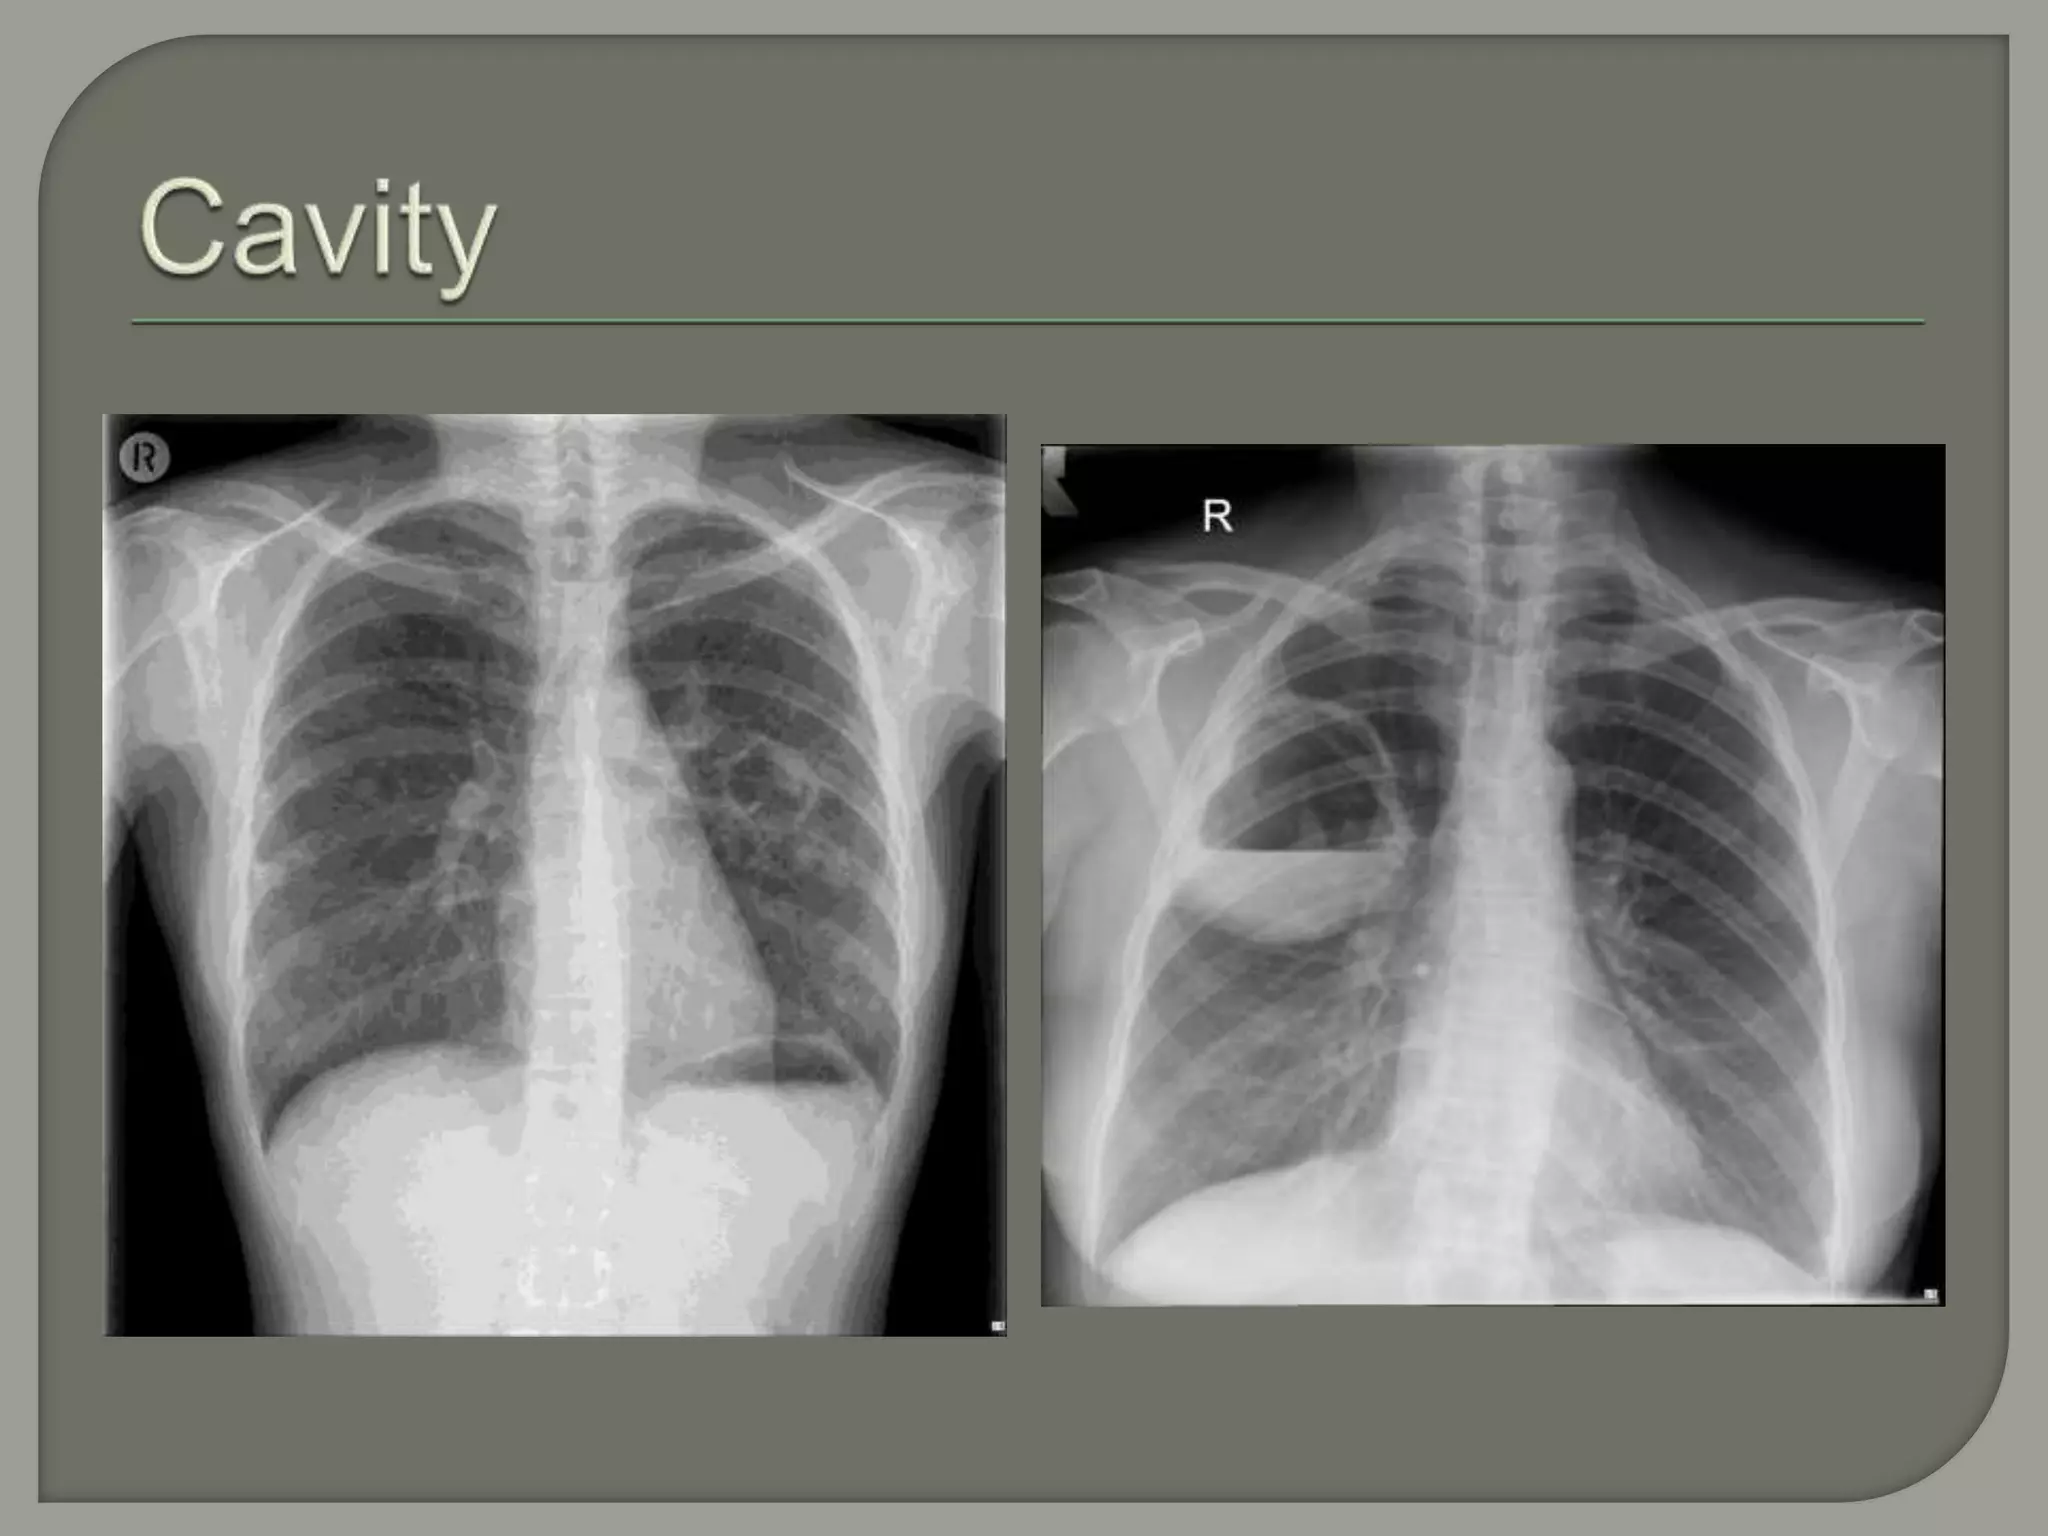

Cavity

Gas-containing space in the lung having a

wall > 1 mm thick

A. Frontal radiograph shows a thin-walled cavity (pneumatocele) in the left lung. B.

CT shows bilateral pneumatoceles and associated ground glass opacities. The

combination is suspicious for Pneumocystis carinii pneumonia

Posteroanterior chest radiographs demonstrating a cavitary lesion (arrow) in Wegener’s

granulomatosis (A).